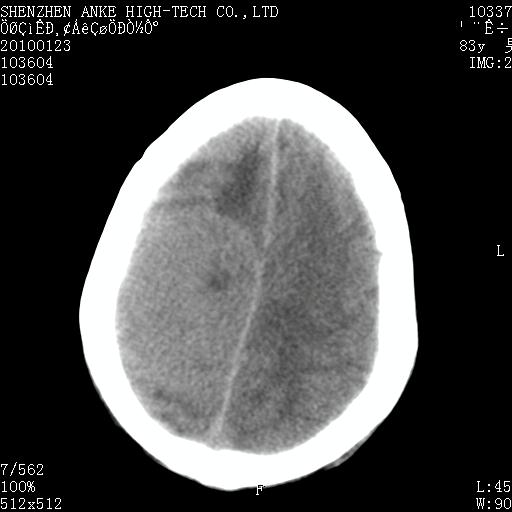

患者:男,83岁,突发意思不清2天。原有脑梗塞病史。

肿瘤卒中,考虑恶性,依次淋巴瘤、转移瘤、恶性脑膜瘤、胶质母等,建议mri。

肿瘤卒中,考虑恶性脑膜瘤可能性大。

脑膜瘤多见于老年女性,与雌激素水平有关。本例虽为老年男性,但是本例还是考虑脑膜瘤的可能性大。

镰旁脑膜瘤卒中